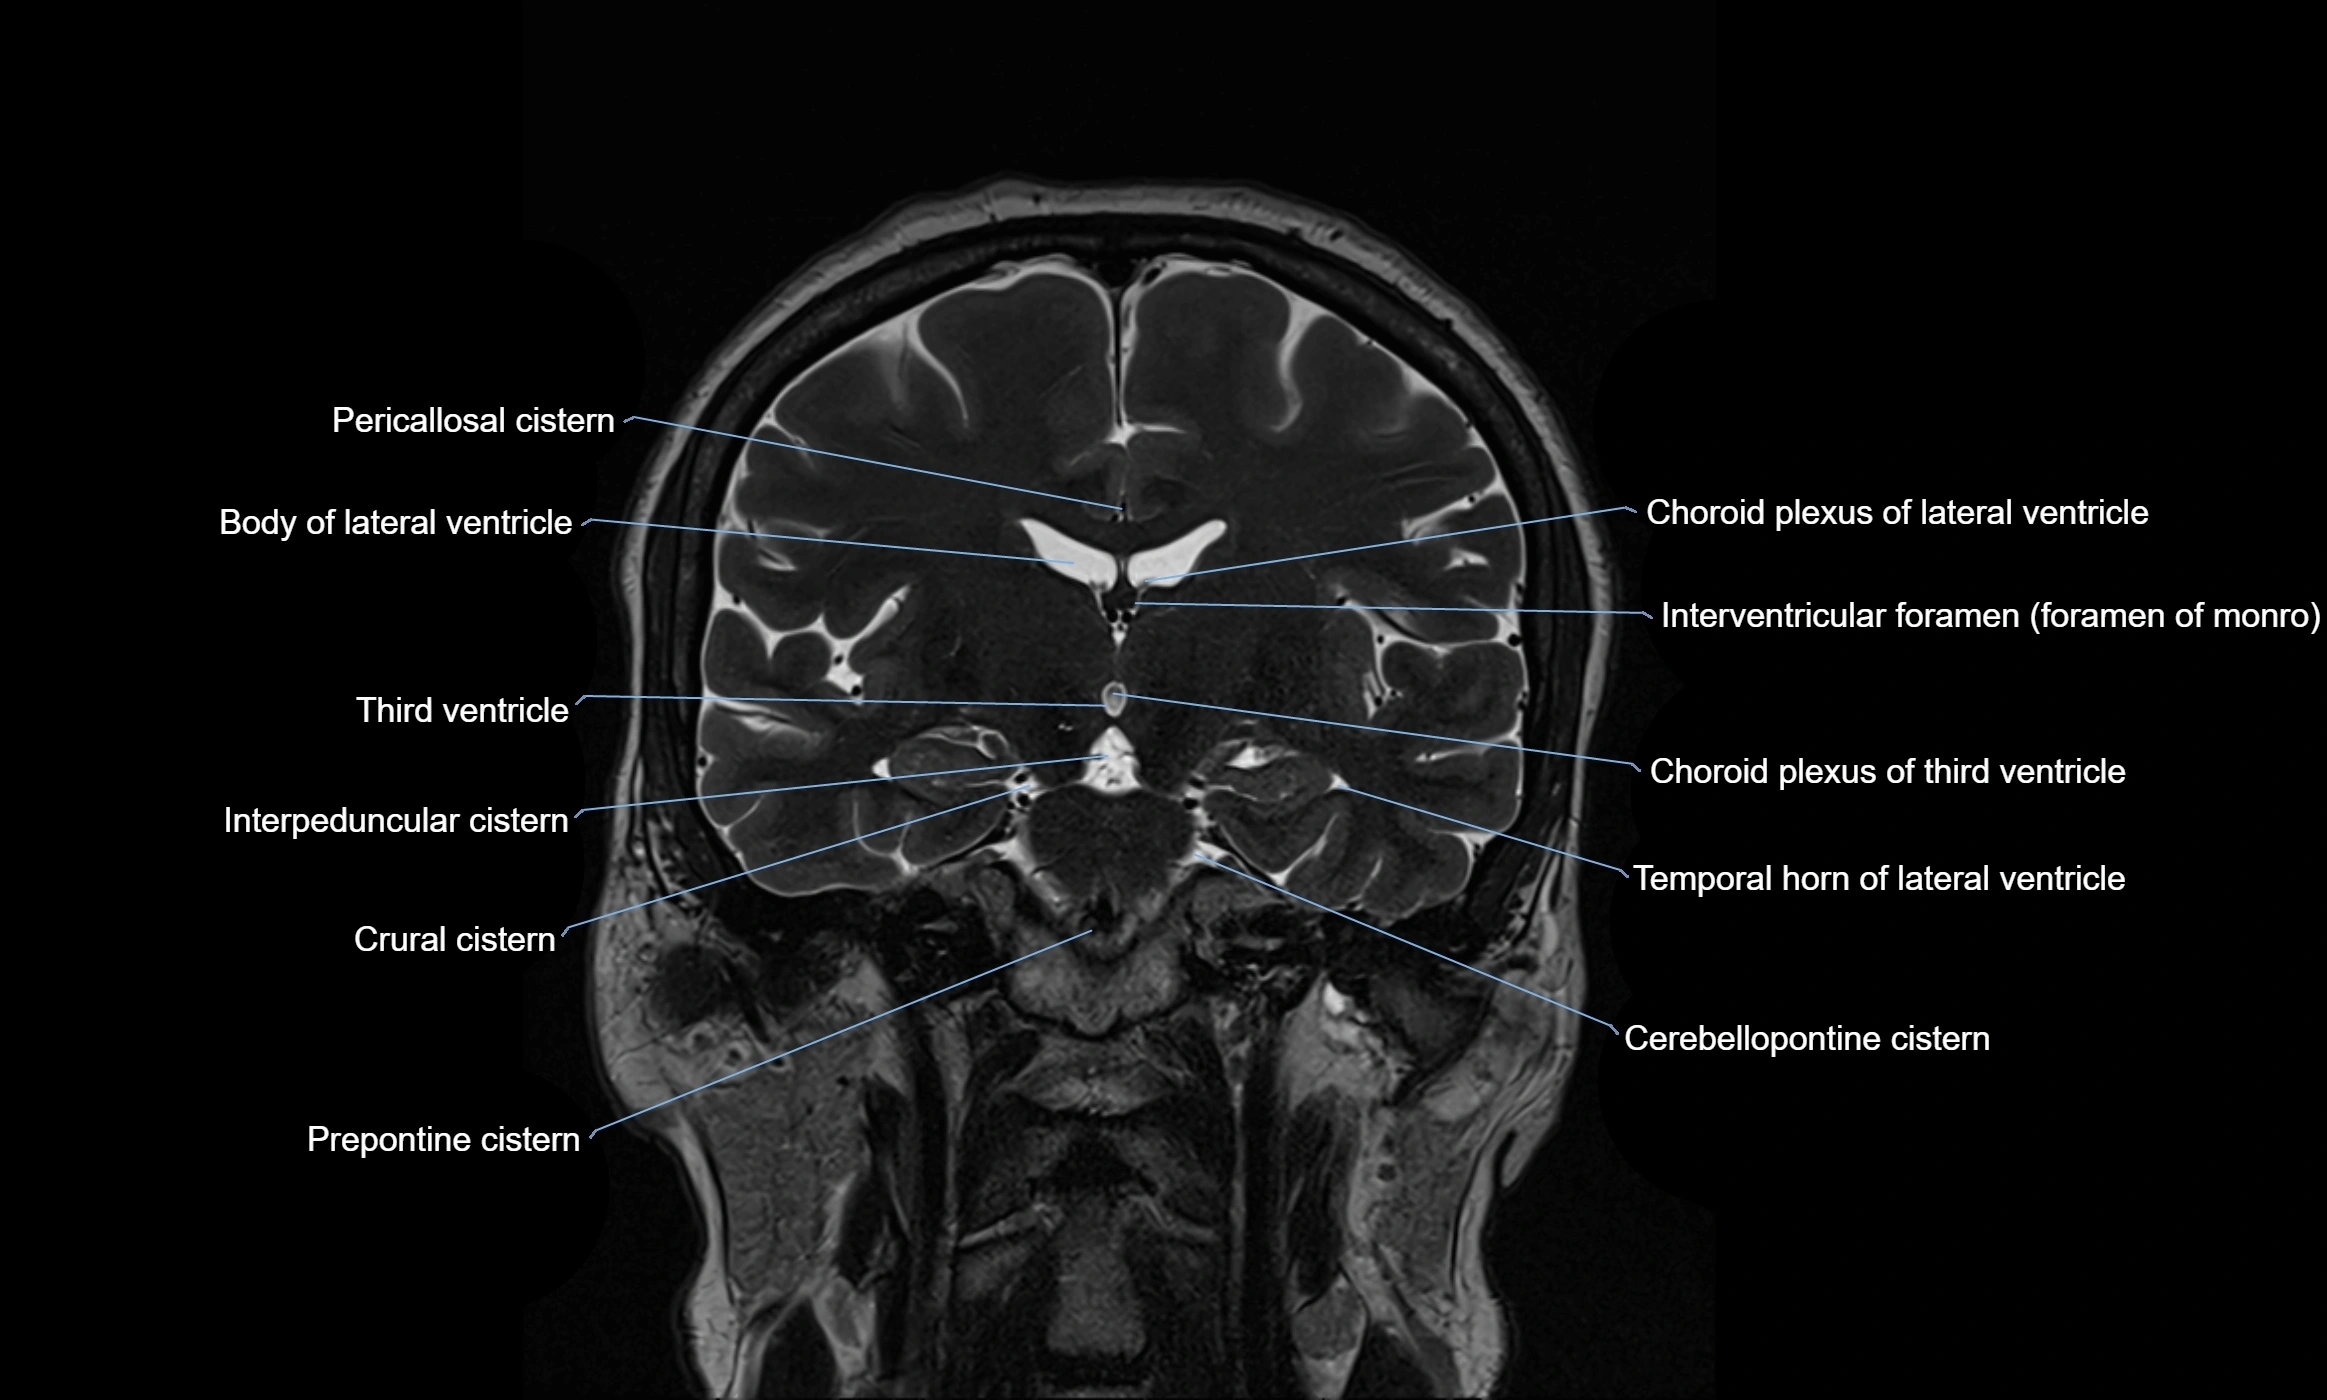

MRI images

image